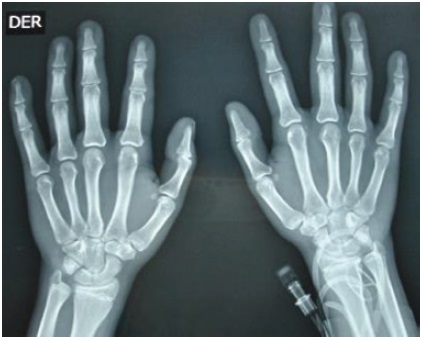

Los laboratorios iniciales muestran un hemograma (Hemoglobina 14,5 g/dL y hematocrito 39,8 %), creatinina (0,65 mg/dL), BUN (17,48 mg/dL), glicemia (72 mg/dL), sodio (137 mmol/L) y uroanálisis normales. Evidencia hipopotasemia (2,6 mmol/L) e hipocloremia (95 mmol/L), cortisol bajo (32 ng/mL con valores de referencia 50-250 ng/mL), renina plasmática baja (4,38 con valores de referencia 20-55 μUI/mL) y un electrocardiograma con hallazgos compatibles con la hipopotasemia (Figura 3). La edad ósea revisada por el método de Greulich y Pyle es de 17 años (Figura 4). En la ecografía renal y de vías urinarias se observa un aumento del tamaño de las glándulas adrenales con diferenciación corticomedular, aspecto más ensanchado de la izquierda, sin evidencia de lesiones focales. El ecocardiograma demostró una cardiomiopatía hipertrófica concéntrica ventricular izquierda no obstructiva, con un aumento de la raíz aórtica e insuficiencia valvular pulmonar leve, sin signos de hipertensión pulmonar. La biomicroscopía del fondo de ojo y agudeza visual se encuentran normales.

En la pubertad normal, la gonadarquia inicia con el aumento del volumen testicular, estimulado por la secreción GnRH a nivel hipotalámico19. Sin embargo, en el caso, el volumen testicular es prepuber asociado al aumento del tamaño del pene y vello púbico avanzado, lo que es indicativo de una pubertad precoz periférica. El exceso de andrógenos por déficit de 11OH, puede virilizar in útero un feto 46XX y producir un fenotipo con ambigüedad genital; en fetos 46XY, el exceso de androstenediona principalmente conlleva a la pubarquia temprana. El tratamiento irregular de corticoides permitió el progreso rápido de la pubertad precoz. Su crecimiento acelerado es evidente por una talla alta para su talla media parental, característica de la pubertad precoz verdadera. El paciente tenía una edad ósea muy avanzada propia de etapas donde el crecimiento óseo está finalizando, lo que permite inferir la repercusión negativa que este proceso tendrá en la talla final del paciente, como describió Cesario et al.,20.